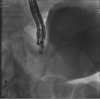

Every trick in the book: EUS angiotherapy for management of refractory bleeding secondary to a complicated duodenal ulcer in a patient with Roux-en-Y gastric bypass